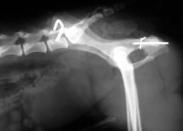

骨盆骨折

骨盆骨折是一種嚴重外傷,占骨折總數的1%~3%,多由高能外傷所致,半數以上伴有合并癥或多發傷,致殘率高達50%~60%。最嚴重的是創傷性失血性休克及盆腔臟器合并傷,救治不當有很高的死亡率,可達10.2%。據統計,骨盆骨折中50%~60%由汽車車禍造成,10%~20%是由于行人被撞,10%~20%為摩托車外傷,8%~10%為高處墜落傷,3%~6%為嚴重擠壓傷。